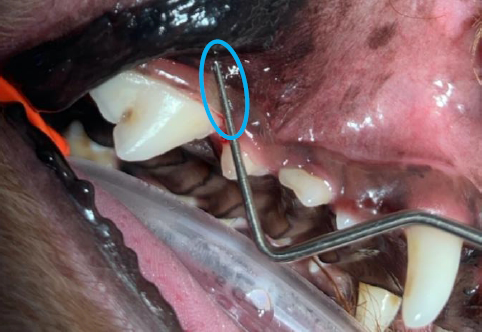

鼻血の原因には、鼻の中のしこり(鼻腔内腫瘍)や、鼻の中の感染症が原因となることもありますが、口の中の病気で鼻血が出ることもあります。口の中と鼻の中は実はかなり近く存在し、特に歯の根っこの部分はかなり鼻に近いため、歯周病などの口の病気が悪化します と、お口と鼻の中がつながる口腔鼻腔瘻管になることもあります。口腔鼻腔瘻管とは、文字通りお口と鼻とがつながる病態で、口の中にいる細菌などの病原菌が鼻の中に容易に感染してしまう状態です。その結果として鼻水が出たり、鼻血、くしゃみが出たりすることもあります。

このフレンチ・ブルちゃんの場合は、鼻血が主訴でしたので、鼻の中にしこりができていないかどうかを CT 検査にて診断し、その際に口の中からの異常のせいで口腔鼻腔瘻管があることがわかりました。口腔鼻腔瘻管の診断に関しては、鎮静や全身麻酔下で「歯周プローブ」という器具を使用することで診断ができます。(左写真) このフレンチ・ブルちゃんの場合は、鼻血が主訴でしたので、鼻の中にしこりができていないかどうかを CT 検査にて診断し、その際に口の中からの異常のせいで口腔鼻腔瘻管があることがわかりました。口腔鼻腔瘻管の診断に関しては、鎮静や全身麻酔下で「歯周プローブ」という器具を使用することで診断ができます。(上写真) |